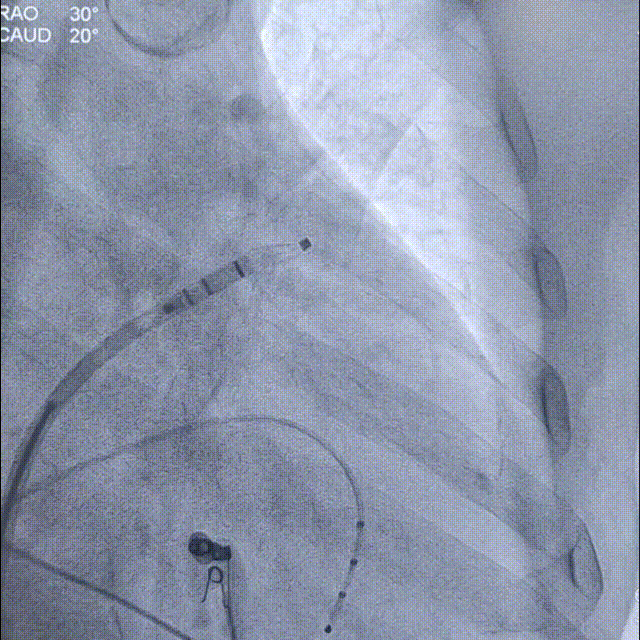

通过LAA造影和工作体位测量,结果显示患者左心耳开口直径为25mm,着陆区直径为20mm,深度为32mm;根据数据,手术团队决定选择Laager®封堵器2429型号进行后续操作;

工作体位造影

画线测量